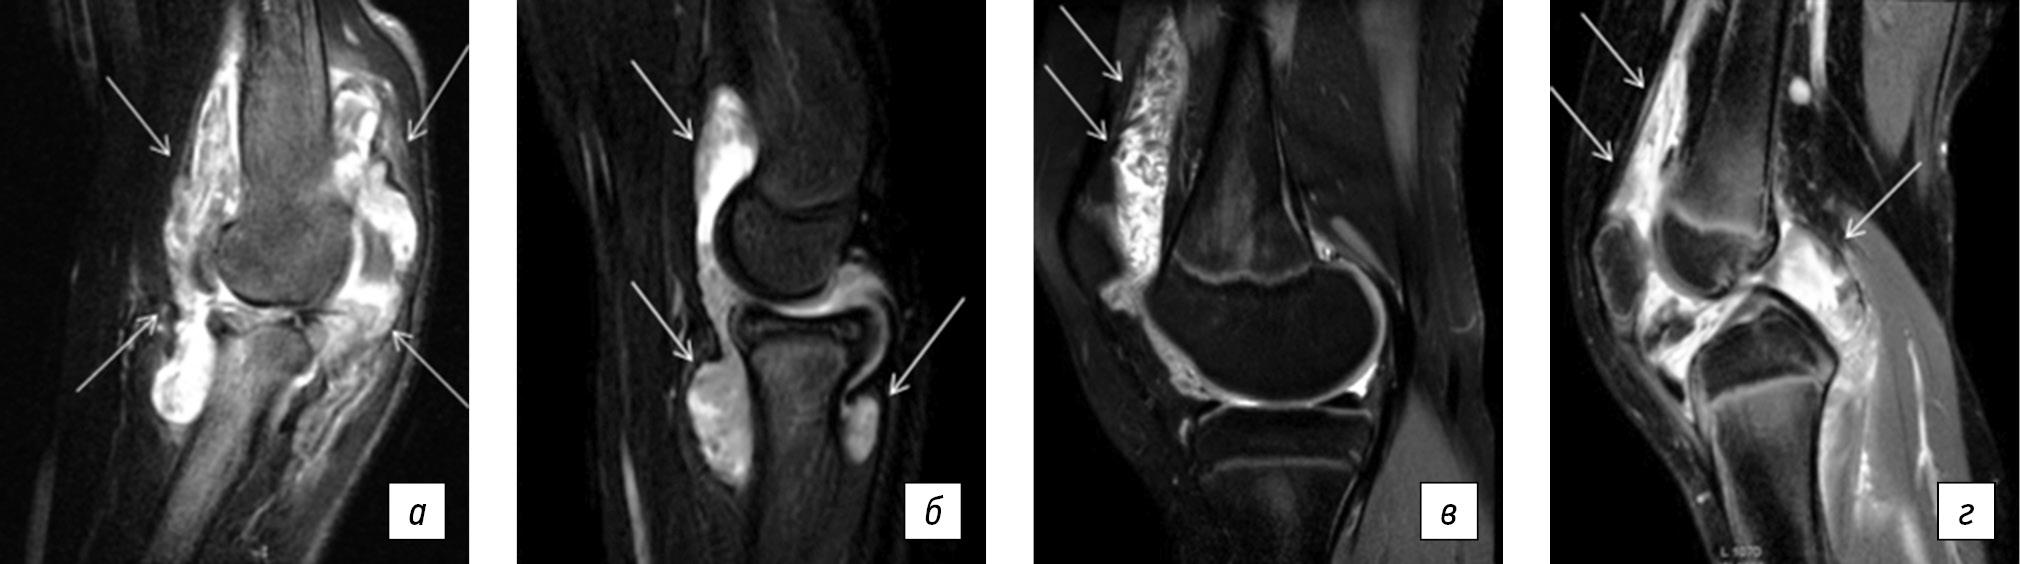

The routine laboratory investigations do not provide useful data and hence do not precisely diagnose these diseases. Magnetic resonance imaging may yield similar findings for both conditions at the early stages (Fig. 2) [11]. However, the assessment of specific laboratory biomarkers in the synovial fluid of children diagnosed with unspecified monoarthritis can suggest a rheumatic etiology, which would eliminate the need for repeated, unjustified invasive procedures. The identification of a laboratory biomarker in cases of undifferentiated monoarthritis, which is indicative of the course of JIA, is therefore of critical importance. To achieve the aforementioned objectives, we undertook a specific approach to the diagnosis and treatment of monoarthritis in children at a single medical center.

Fig. 2. Knee and elbow magnetic resonance imaging with short tau inversion recovery in pediatric patients (Source: Author’s archive). a, pigmented villonodular synovitis of the elbow, heterogeneous total synovial proliferation with extensive capsular distension; b, juvenile idiopathic arthritis of the elbow, subtotal synovial proliferation with nodular degeneration; c, pigmented villonodular synovitis of the knee, heterogeneous nodular synovial proliferation; d, juvenile idiopathic arthritis of the knee, heterogeneous total synovial proliferation with capsular distension.